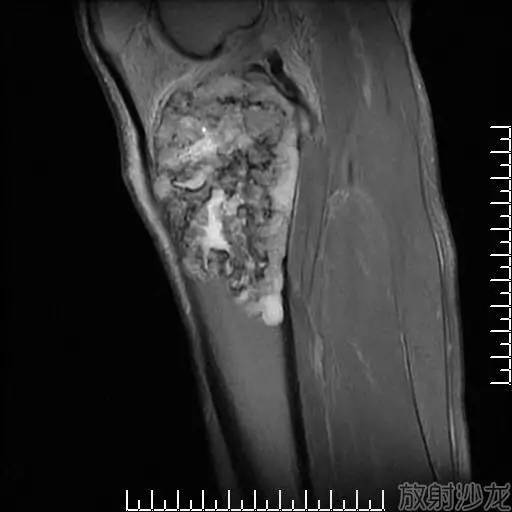

本病主要累及软骨内成骨的骨骼,特别是四肢骨,表现为透明软骨的变性坏死及伴随的吸收、修复性变化。软骨细胞常见凝固性坏死,细胞核固缩、碎裂、溶解消失后,残留红染的细胞影子。进而残影消失,基质红染,成为灶状、带状的无细胞区。坏死区还可进一步崩解、液化?;邓涝钪芪Т婊畹娜砉窍赴S蟹从π栽錾?,形成大小不等的软骨细胞团(图6)。在邻近骨组织处,坏死部位可发生病理性钙化;初级骨髓的血管和结缔组织侵入坏死灶内,出现机化、骨化,最终为骨组织软骨坏死以累及成熟中的软骨细胞(肥大软骨细胞)为主,呈现近骨性分布?;邓览┐笫?,也会波及其他层次的软骨细胞。坏死灶常为多发性,大小不一,呈点状、片状或带状。

(2)骺板软骨病变:

骺板软骨的坏死主要发生于肥大细胞层,重者可贯穿骺板全层。骺板深层发生坏死后,该部由干骺端来的血管不能侵入,正常的软骨内成骨活动停止;但坏死灶上方存活的增生层软骨细胞还能继续增生、分化,导致骺板的这一局部增厚。在坏死灶的近骨边缘常发生退行性钙化,并可沿坏死灶的干骺端沉积骨质,形成不规则的骨片或横骨梁,表示正常骨化过程停顿。而骺板的其他部分成骨活动仍在继续,因而造成骺板的厚薄不均和骨化线的参差不齐。

当坏死灶贯穿整个骺板时,由骺核和干骺端两个方向进行坏死物的吸收、机化和骨化,终于导致骺板提前骨性闭合,该管状骨的纵向生长早期停止,造成短指(趾)或短肢畸形。

由于干骺端血管丰富,骺板软骨坏死后的吸收、机化和骨化发展较为迅速,因而其X线影像在较短时间(数月至1年)内可明显加重或好转愈复。

(3)关节软骨病变:

关节面软骨也以同样的营养不良性病变开始,渐渐发生软骨破坏。关节面粗糙不平,常发生软骨溃疡,影响关节活动,诱发疼痛。部分软骨可脱落构成“关节鼠”。重症者,关节软骨边缘部增殖而呈盘状隆突,其后常有化骨,因而关节部变粗大?;ひ灿腥廾丛鲋?。绒毛脱落可成为游离体。软骨周围的滑膜也常肥厚,可构成软骨及赘骨,而致骨端更增大,边缘不规则。此外,骨质常呈普遍疏松,骨小梁破坏、吸收,可形成空泡和囊肿样结构,并可伴有增生性改变。骨质明显变薄,可疏松呈海绵状。骨髓腔扩张,髓内常出现坏死灶和空泡。肌肉、脏器和内分泌腺均伴有以营养不良性退行性变为主的病变。

和骺板软骨的坏死灶一样,关节软骨的病变也呈近骨性分布,即首先是深层成熟中的软骨细胞受累,常形成典型的带状坏死。由于此部坏死物质的吸收较为缓慢,坏死存在时间较久,故坏死灶周边部增生的软骨细胞团往往更引人注目。在较大的坏死灶当坏死物质崩解、液化后,形成裂隙或囊腔。在重力和摩擦等机械作用下,其表层软骨组织易成片剥落(分离性骨软骨炎),形成关节游离体(关节鼠),而局部关节面则留下大小不等的溃疡。重者病变部关节软骨可全层破坏消失,造成大片骨质裸露。在关节面的边缘部分,与软骨坏死相伴随常有软骨增生反应,导致关节边缘部分增厚,且可骨化而形成骨性边缘增生物(图11)。由此而引起患者骨端增大、关节变形和活动受限。后期关节滑膜结缔组织增生、钙化和骨化,更加重了关节粗大。由于关节软骨的变性坏死、崩解剥落和修复增生等过程反复进行,以致晚期病例表现为变形性关节病的改变。但从未见发生骨性关节强直。用单克隆免疫组化法显示,关节软骨表层的Ⅱ型胶原表达减少,Ⅰ型胶原增多;增生的软骨细胞团有Ⅰ、Ⅱ、Ⅲ、Ⅵ型胶原表达。

关节软骨坏死的吸收机化只能从骨板壳的正常缺口处开始,修复反应相对较弱,病变发展较为缓慢。因此,在X线下关节面(骨端)的病变往往比干骺端的病变显影较晚,修复过程发展缓慢,历经较长时间而变化甚微。